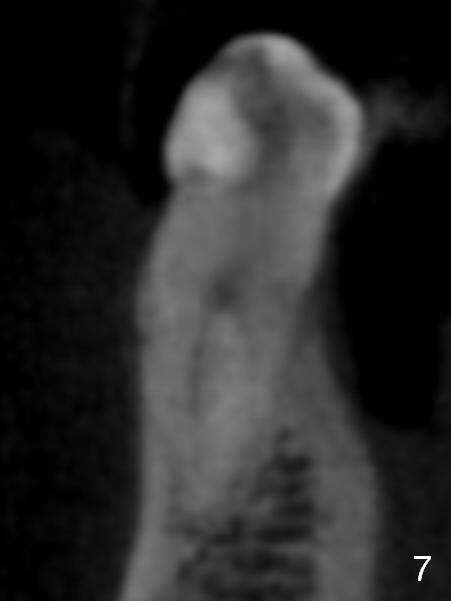

In fact CBCT has ben taken for #14 RCT and is reviewed prior to this case. If CT were reviewed, finding the extra canal would be easier (Fig.6 coronal section). It appears that the apical canals are blocked (Fig.7). The canal is split at the middle of the root, as shown in Fig.8,8' (axial upper section, as shown by the upper dashed line in Fig.6) and in Fig.9,9' (axial lower section, as shown by the lower dashed line in Fig.6). The buccal canal should not have been debrided with 40/.04 rotary file (30/.04 would have been better). In all, the tooth has two fused roots (Fig.3,9,9').